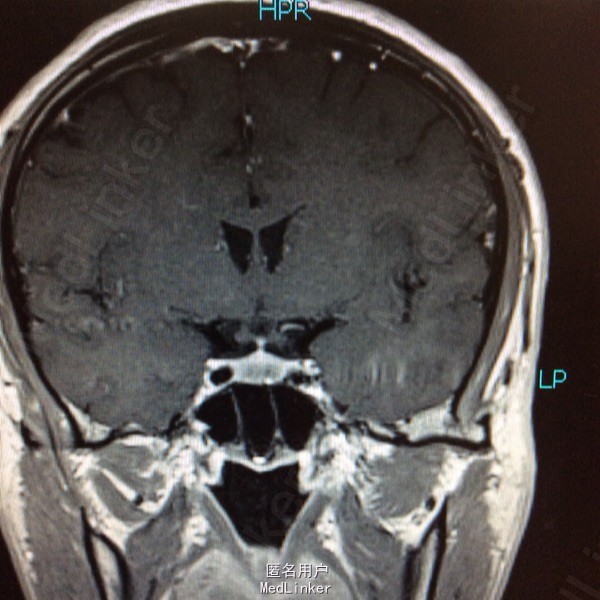

男性,31岁,头痛起病,无恶心呕吐,无视力改变。

查体未见明显阳性体征,发育正常 头颅CT提示鞍区少量出血 MRI增强提示鞍区占位病变,大小约0.8*1.5cm 考虑垂体瘤卒中

术前诊断:垂体瘤 择期行经蝶入路垂体瘤切除术 术后病理提示垂体腺瘤